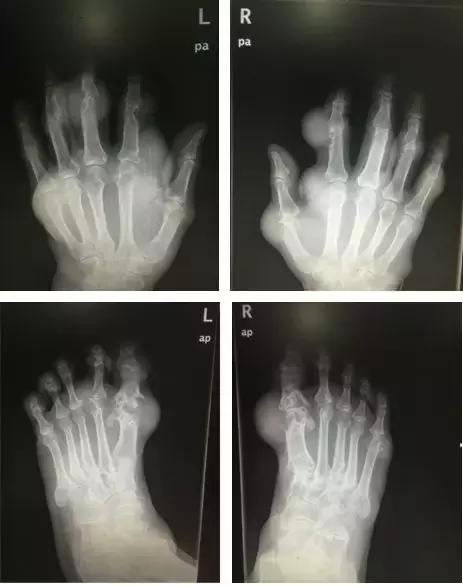

这一天,困扰他4年多、布满双手双脚的痛风石,终于被切掉了!

“十根手指,终于能并拢了!”

手术后的小张,手指和双脚的外观、功能,都得到了明显的改善。

痛风石的典型部位在耳廓,也常见于足趾、手指、腕、踝、肘等关节周围,隆起于皮下,外观为芝麻大到鸡蛋大的黄白色赘生物,表面皮肤菲薄,破溃后排出白色粉末状或糊状物,经久不愈,部分患者继发感染。